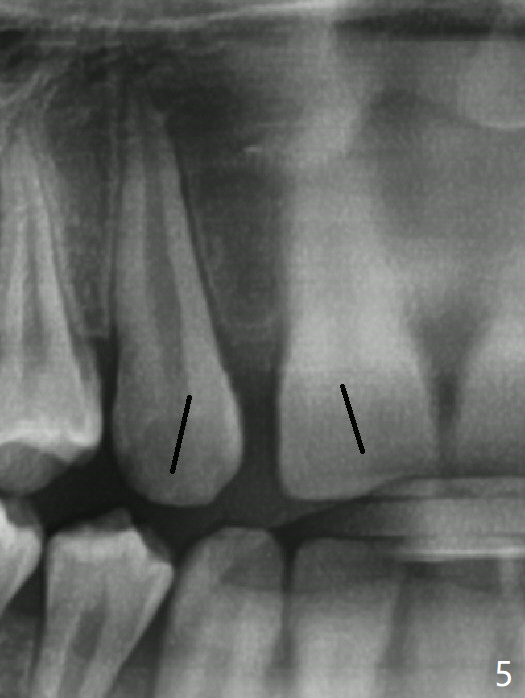

A 14-year-old man requests ortho because of crowding lower anterior and UR missing lateral (Fig.1-4). Open space for the future implant at UR2 will correct upper midline deviation (Fig.1) and change Class II malocclusion to I on the right (Fig.6, as compared to Fig.7). To control UR1,3 root torque, bracketing on these 2 teeth will be intentionally off (Fig.5). The treatment will take ~ 2 years. Prior to implantation at UR2, what type of prosthesis should be made?